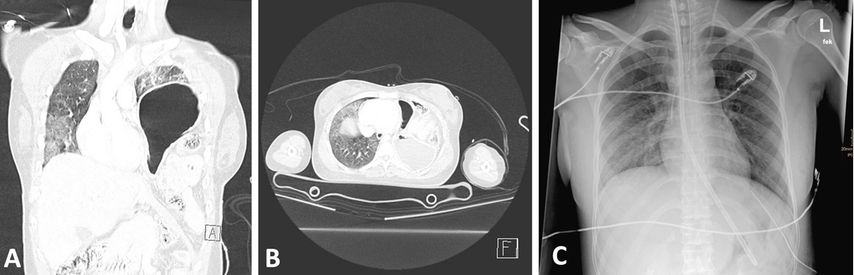

Abb. 1: Eine 25 Jahre alte Patientin nach seitlichem Aufprall mit linksseitiger Zwerchfellruptur und Migration der Oberbauchorgane in den Thorax. Koronare Schichten zeigen die Magenblase im linken Hemithorax (A). Axial ist das Ausmaß der Organmigration dargestellt (B). Lungenröntgen 4 Tage nach der unmittelbar posttraumatisch durchgeführten Rekonstruktion des Zwerchfells (C)